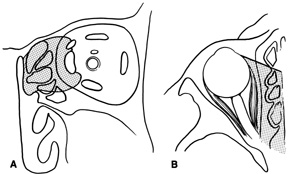

intraconal space lateral to the optic nerve (Fig. 8A, B).  Fig. 8. Coronal (A) and axial (B) views in an illustration of areas (shaded) amenable to lateral

orbitotomy. Fig. 8. Coronal (A) and axial (B) views in an illustration of areas (shaded) amenable to lateral

orbitotomy.